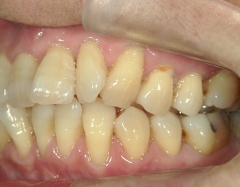

矯正歯科 治療前矯正歯科 治療前

矯正歯科 治療前